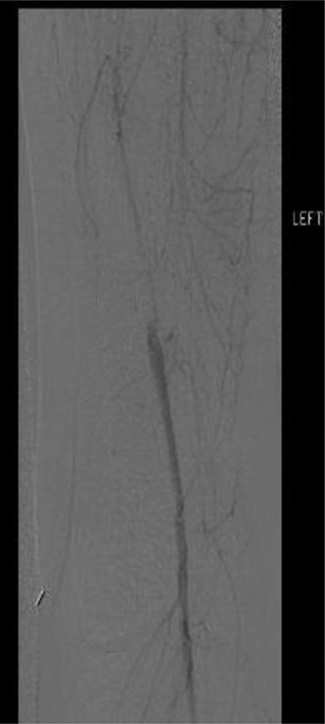

Workup began with noninvasive studies of the left lower extremity displaying aortoiliac occlusive disease and infrainguinal disease. Aortogram demonstrated a severely calcified aorta, patent left common iliac and proximal hypogastric arteries, with occlusion of the left external iliac, left common femoral and left superficial femoral arteries (Fig. 1). The right iliac system was patent apart from an occluded right hypogastric artery. A selective left lower extremity angiogram demonstrated reconstitution of the mid-to-distal profunda femoris artery (Fig. 2) to the proximal above-knee popliteal artery at the adductor hiatus (Fig. 3). Extensive collateralization was appreciated in the pelvis and lower extremity, between the residual left hypogastric artery and profunda femoris artery. Endovascular revascularization attempts were unsuccessful.

Selective left lower extremity angiogram demonstrating patent mid-to-distal profunda femoris artery and its collaterals

Selective left lower extremity angiogram demonstrating reconstitution of the above-knee popliteal artery at the adductor canal